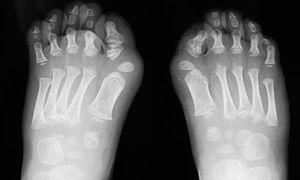

Caso 1. Varón sin antecedentes de interés que en julio de 2003, a los 30 meses de edad, ingresó por una tumoración pequeña, mal definida y dolorosa en región cervical derecha, que coincidiendo con la varicela se extendió hacia la escápula. Estaba afebril y tanto la analítica como el cariotipo fueron normales. Se evidenció hallux valgus (fig. 1), clinodactilia y una calcificación de 2 x 1 cm en la eminencia tenar de la mano derecha (fig. 2). La ecografía y la resonancia magnética revelaron engrosamiento de la fascia. La biopsia resultó compatible con fascitis nodular versus seudotumor inflamatorio. Por la sospecha de FOP, en agosto inició tratamiento con alendronato 20 mg/semana de forma continuada y con corticoides e ibuprofeno en los empeoramientos clínicos. En junio de 2004 la enfermedad había progresado y se evidenciaban masas de consistencia dura a lo largo de la espalda, en regiones paravertebrales y bajo la axila derecha, con importante limitación para la movilidad del brazo, que apenas podía separar del tronco y de la columna cervical, que sólo conservaba el movimiento de flexión.

Figura 1. Hallux valgus.

Caso 2. Niña diagnosticada de FOP a los 3 años por limitación para la flexión de rodilla derecha y calcificaciones en tejidos blandos, hallux valgus y clinodactilia. Los antecedentes familiares carecían de interés. Nos fue remitida desde el servicio de Ortopedia en 1994, a los 13 años, por dolor mecánico en ingle derecha. La exploración mostró contractura en extensión y ausencia de movilidad del codo y la rodilla derechos, flexo de 40° no reducible en la cadera derecha, e imposibilidad para las rotaciones, aunque flexionaba hasta 90º en la cadera izquierda. La capacidad para deambular estaba muy limitada. La radiografía de caderas demostró calcificaciones de tejidos blandos (fig. 3). Desde los 15 años se objetivó trastorno ventilatorio restrictivo moderado. El cuadro progresó a pesar de tratamiento con alendronato 10 mg diarios y de la administración de indometacina y corticoides en los episodios de dolor y tumefacción. A los 20 años fue perdida para el seguimiento.